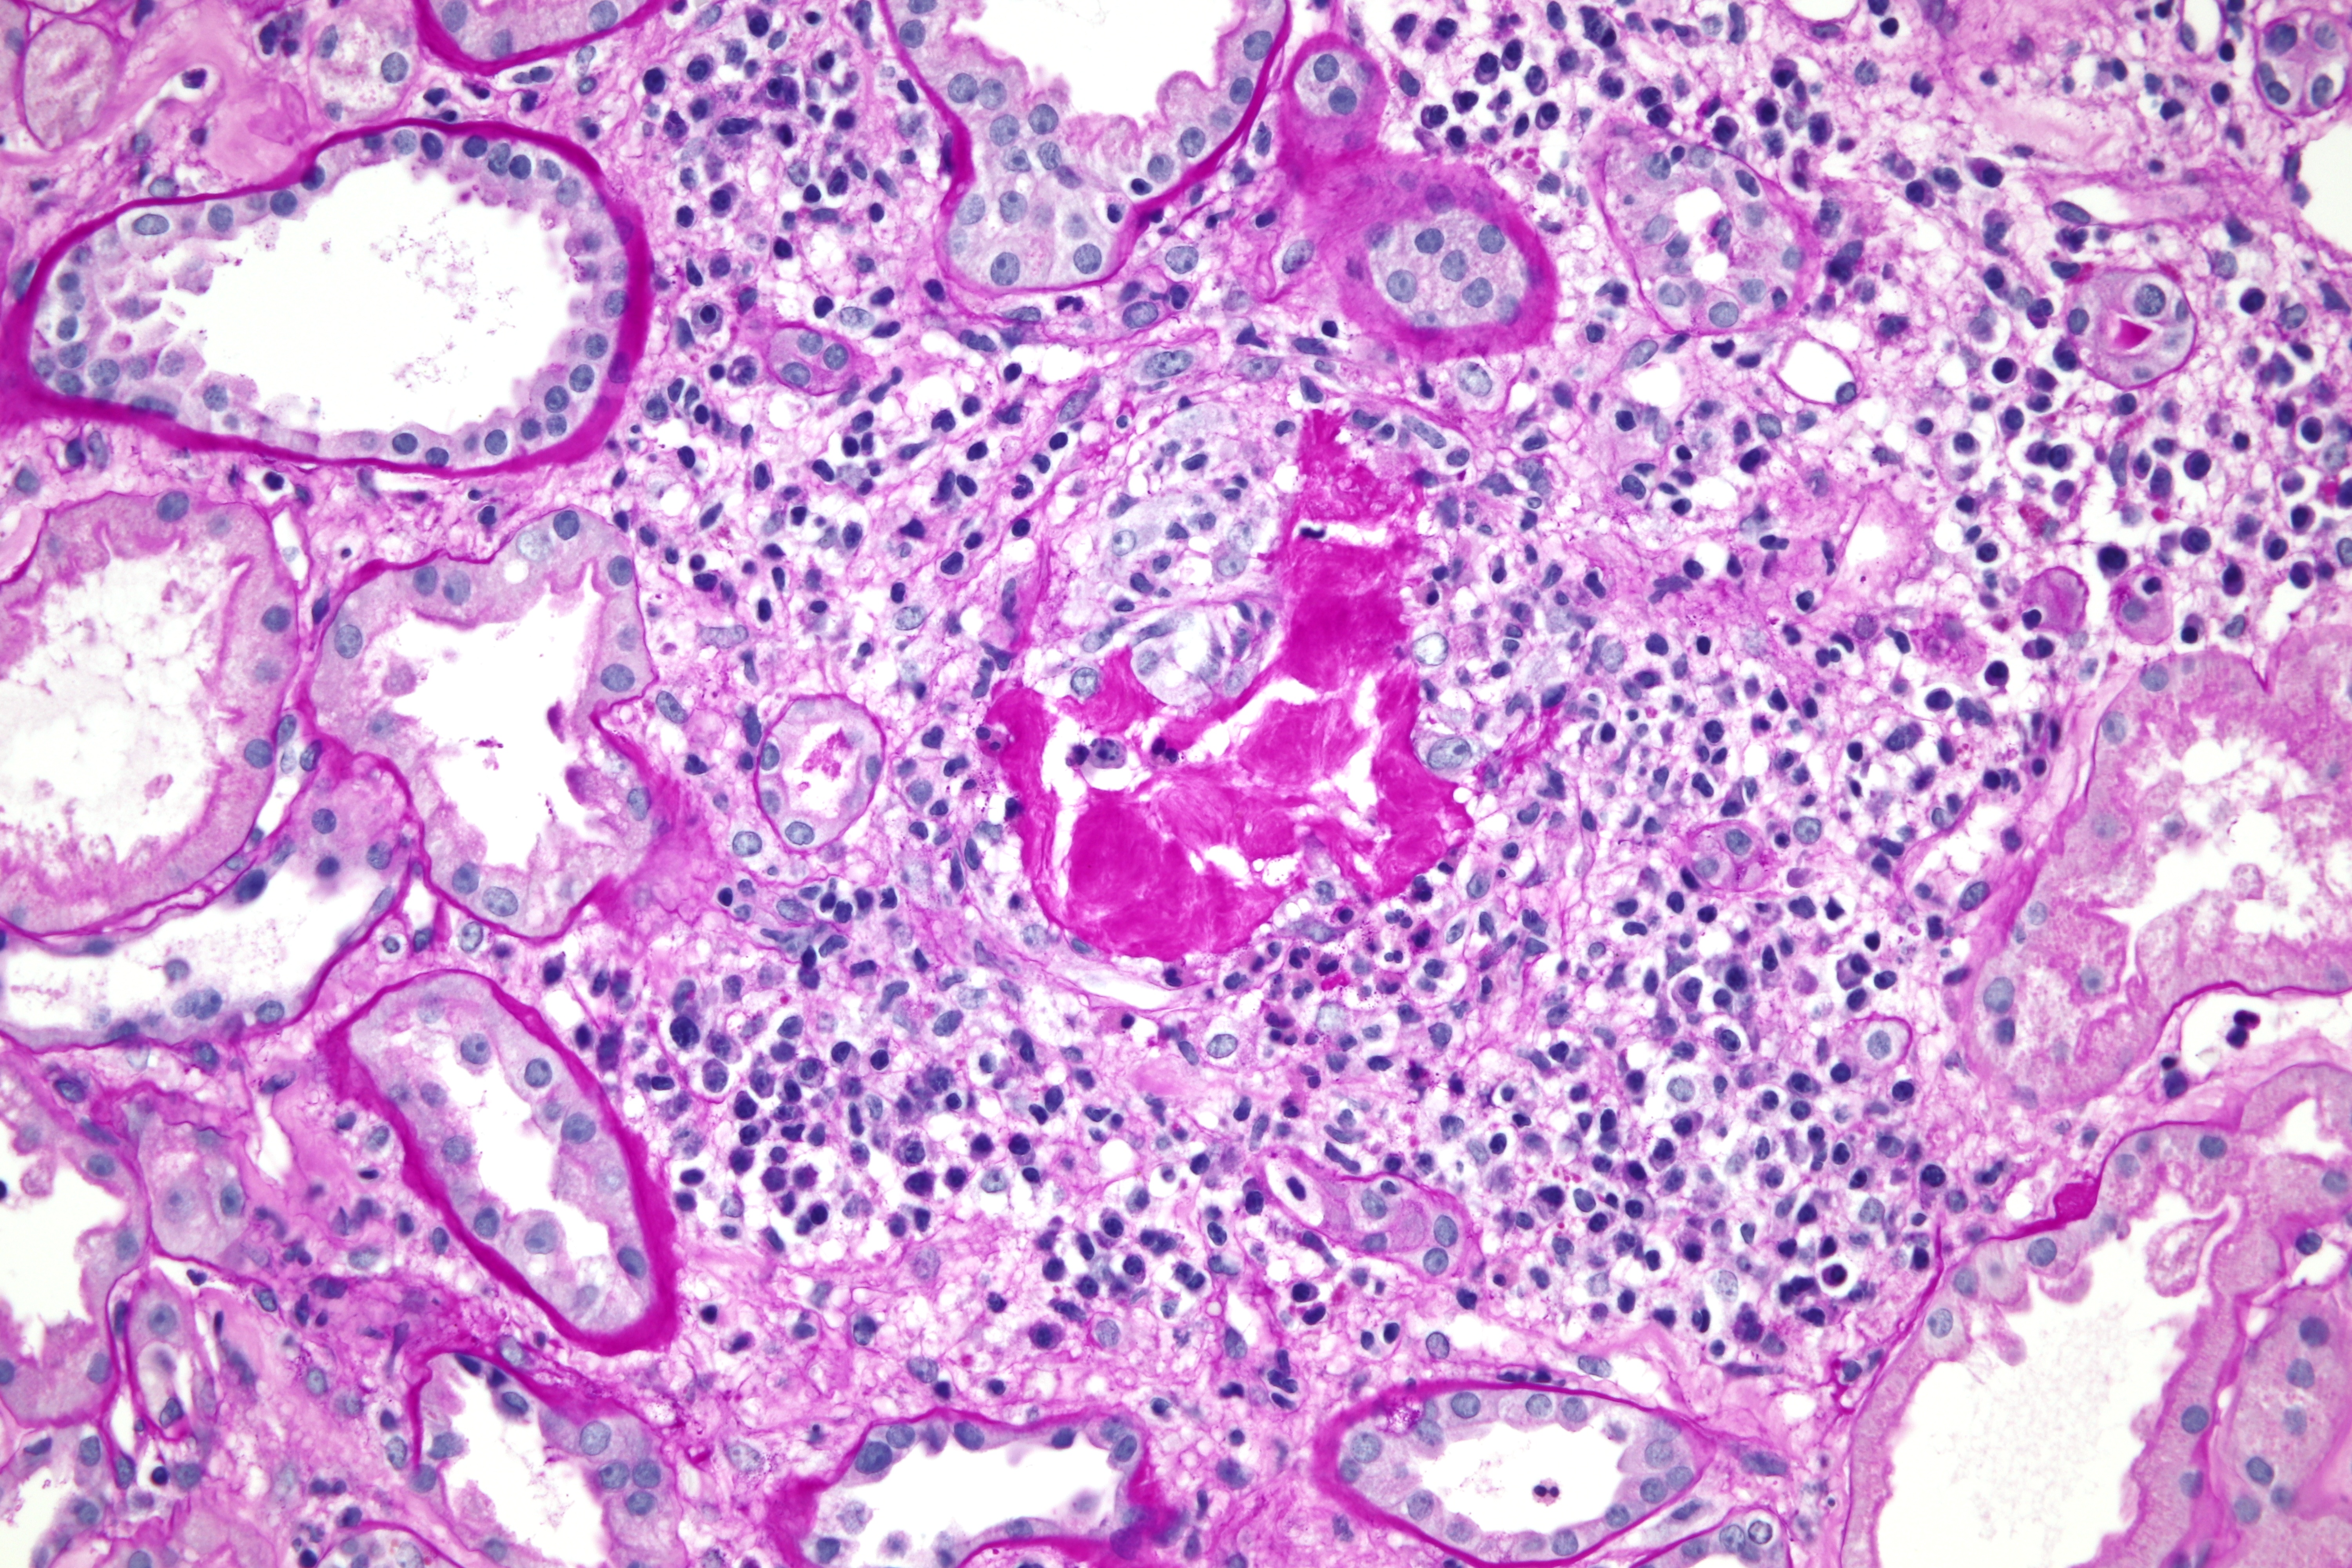

OBR. 2 Bioptický nález, barvení Periodic Acid Schiff – zánětlivá celulizace intersticia s destrukcí tubulu a Tammovým–Horsfallovým proteinem v intersticiu.

Zde byl doplněn základní imunologický screening s negativním nálezem, vyjma hodnoty C3 složky komplementu lehce snížené na 0,87 g/l. Následně jsme proto provedli renální biopsii, v níž dominovala morfologie akutní tubulární nekrózy (ATN) s četnými žlučovými válci v tubulech a projevy intrarenální obstrukce s akumulací Tammova–Horsfallova proteinu v intersticiu (obr. 1 a 2). Bioptický nález byl tedy uzavřen jako obraz cholemické nefrózy. Třetí den po renální biopsii vzhledem k dalšímu nárůstu hodnot dusíkatých katabolitů a při známkách hyperhydratace byla zahájena intermitentní hemodialýza. Celkem jsme provedli pouze dvě procedury, jelikož záhy došlo u pacienta k obnově renálních funkcí a k rozvoji mírné polyurické fáze renálního selhání. Desátý den od biopsie byl pacient v dobrém klinickém stavu propuštěn. Při poslední ambulantní kontrole dva měsíce od propuštění přetrvává elevace hodnot kreatininu 110 µmol/l, bilirubin i jaterní enzymy jsou již v normě.